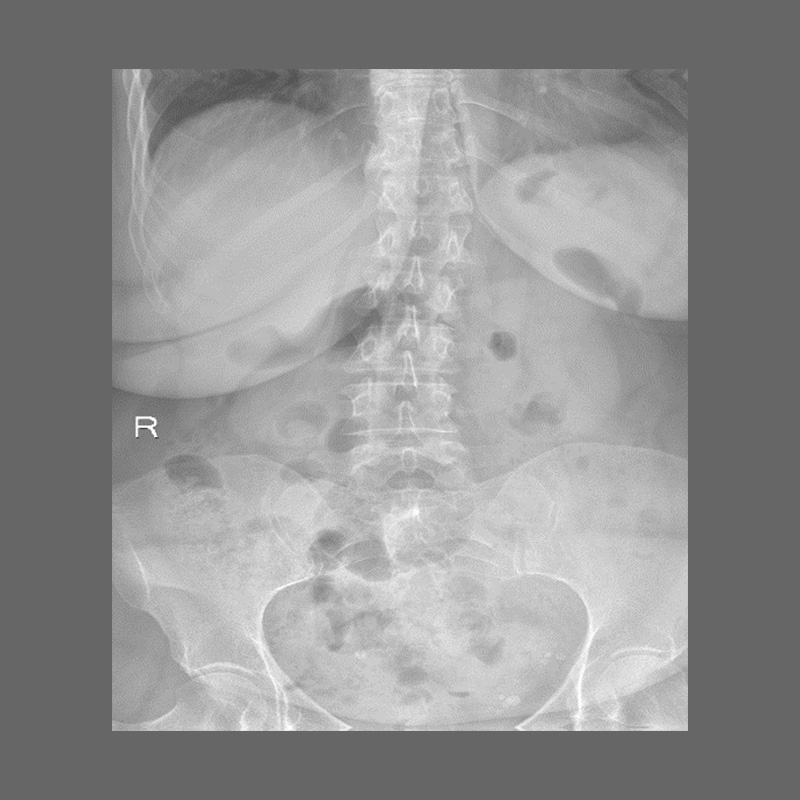

КЛІНІЧНА ГАЛЕРЕЯ GENÈVE 40M: